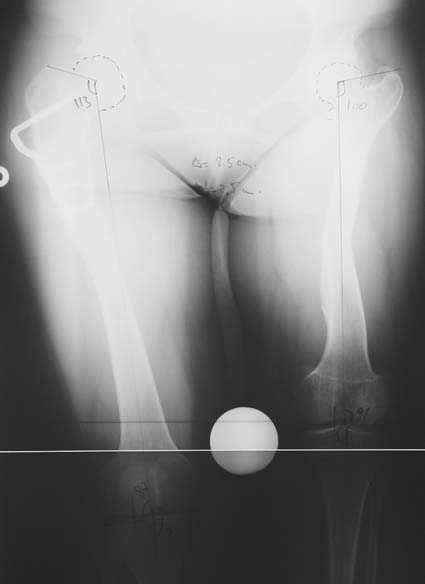

Bu işlemin ne zaman ve hangi kemik segmentlerine uygulanacağı değişik metodlarla (Gren-Anderson şeması; Moseley eğrisi; Paley’in multiplier metodu gibi.) tedaviyi yapacak doktor tarafından hesaplanmalıdır. Yetişkinlerde büyüme çekirdekleri kapanmış olduğu için epifizyodez bir seçenek değildir. Yetişkinde uzun bir bacağı kısaltmak için kemikten bir parça cerrahi olarak çıkartılmalıdır. Bu genellikle femurda (uyluk kemiği) yapılır ve kemik intramedüller çivi ile tespit edilir. Bu yöntemin en büyük avantajı 5cm´den az uzunluk farklarında boy eşitliğini hemen sağlamasıdır. Hem epifizyodezin hem de kısaltmanın ortak dezavantajı hastanın toplam boyunun kısalmasıdır. 5cm’ den fazla kısaltma tavsiye etmediğimiz için boy kaybı hiçbir zaman 5 cm’ den fazla olmamaktadır. 5cm’den daha az boy farklılıkları için kısaltma veya epifizyodez ameliyatı olmak istemeyen hastalarda bacak boyunu eşitlemek için bacak uzatma işlemi tercih edilmelidir. İkinci bir uzatma ihtiyacını azaltmak veya uzatma miktarını azaltmak için epifizyodez ve kısaltma uzatma ile kombine ederek uygulanabilir.